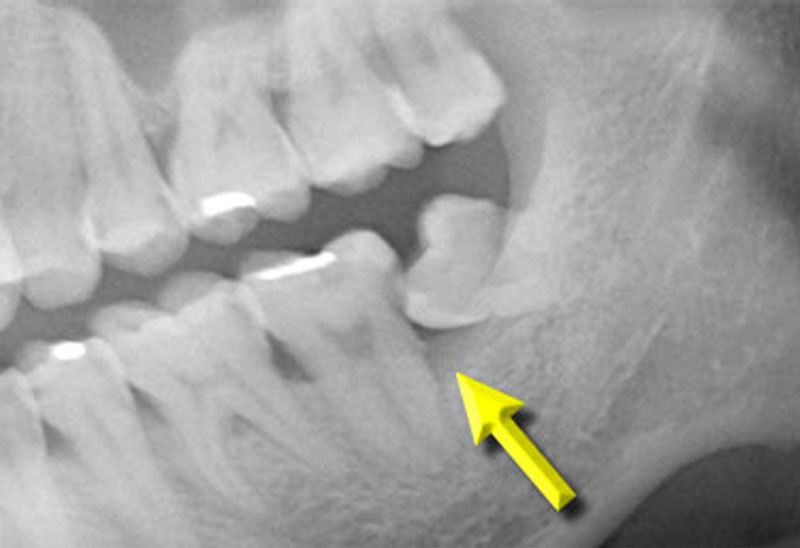

左下顎水平智齒造成前面的第二大臼齒牙根蛀牙和牙周病,前面的第二大臼齒牙根蛀牙往往沒辦法填補,嚴重的需要拔牙。